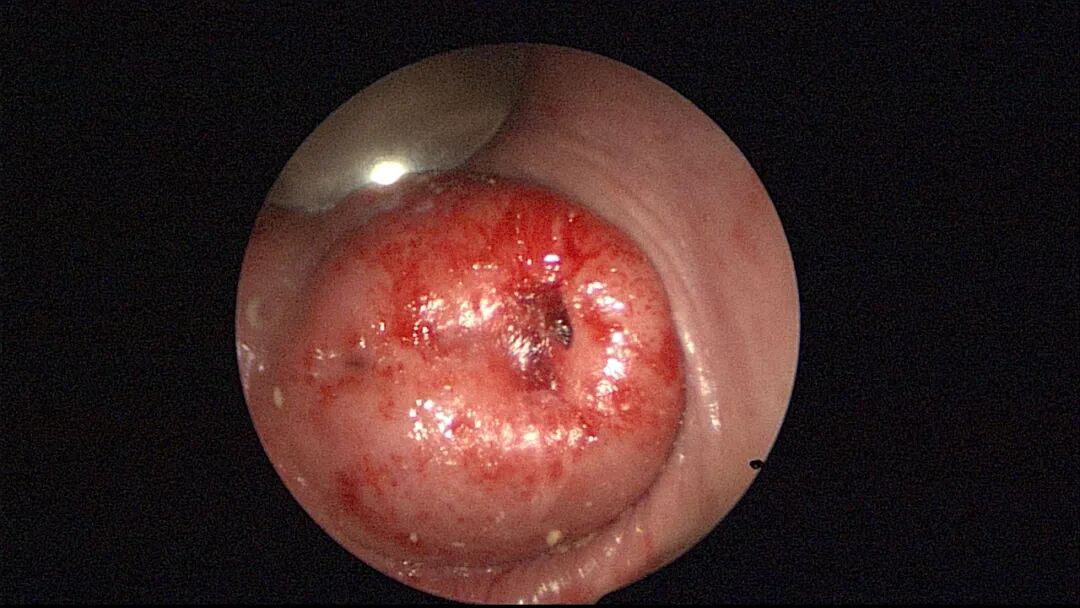

大多数宫腔镜检查或小手术比较简单,属1~2级手术。直径大于2.5cmⅡ型及以上分型粘膜下肌瘤、胚物残留血供丰富或合并动静脉瘘、胎盘粘连胎盘植入、重度宫腔粘连、绝经时间长生殖器官明显萎缩病人(节育环嵌顿、粘膜下肌瘤、息肉等)、子宫极度前屈后屈侧屈等病例,属3~4级手术,手术可能很困难,手术时间较长,容易出现并发症。宫腔镜手术彻底性跟手术难度及手术效果密切相关,宫腔镜手术不彻底常见,比如节育环残留、胚物残留、纵膈残留、粘连残留等,可能引起感染或医疗纠纷。宫腔镜手术过度少见,纵膈切除过度、分粘过度、内膜切除过度易引起出血及穿孔,熟悉子宫局部解剖、B超或腹腔镜监护可避免或减少手术过度。宫腔镜手术失败罕见(资深医生常能找到解决办法):宫颈无法扩张致手术失败、膨宫不良致手术失败或手术不彻底、术中无法找到节育环放弃手术等偶有发生,需与患者及家属充分沟通,择期再做手术,不要在一条道上走到黑。

外院取环失败,宫颈暴露困难,缝合牵拉宫颈,尖刀片切开宫颈前唇,扩宫棒顺利扩开宫颈